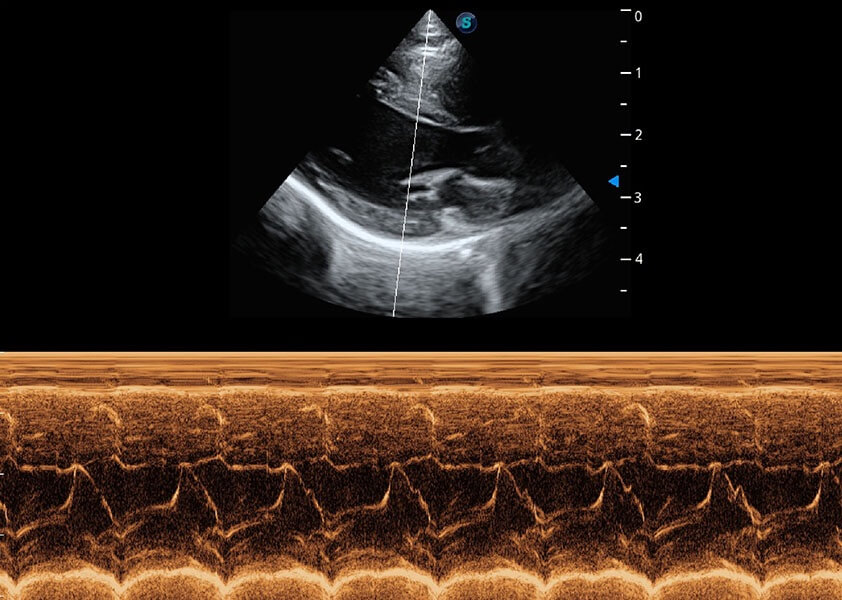

ProPet 60 作为一款高端台式动物超声设备,为动物医生的日常诊断提供了一系列贴合动物临床需求、解决临床实际问题的高级成像功能。凭借全系列高清探头,满足医生对腹部、心脏、生殖、浅表、肌骨等成像的所有需求,切实帮助您提升检查效率,提高诊断信心。

动物是人类最亲密的朋友和最值得信赖的伙伴。环球UG官网也一直致力于探索动物专用的超声影像解决方案。 全新推出的ProPet系列,是环球UG官网在动物超声影像智能化、专业化、精准化的一次跨越式革新。动物不能用言语来表述自己的不适,通过超声影像,ProPet系列搭建了动物医生与不同物种沟通的“桥梁”,为动物医生注入了“治愈之力”。